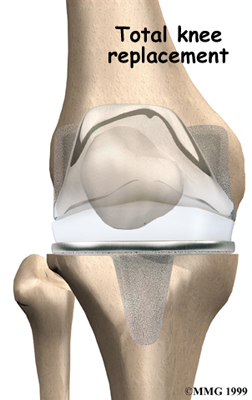

Artificial Knee Replacement

An artificial knee replacement is the ultimate solution for advanced knee OA.

Surgeons prefer not to put a new knee joint in patients younger than 60. This is because younger patients are generally more active and might put too much stress on the joint, causing it to loosen or even crack. A revision surgery to replace a damaged prosthesis is harder to do, has more possible complications, and is usually less successful than a first-time joint replacement surgery.

Related Document: FYZICAL Falmouth's Guide to Artificial Joint Replacement of the Knee